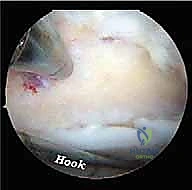

الخطوة 4: الإجراء العلاجي الدقيق (Therapeutic Intervention)

بناءً على التشخيص، يتم إجراء العلاج اللازم بدقة متناهية:

* استئصال العظم الزائد (Os Trigonum Excision): يتم فصل العظم الزائد بحذر عن الأنسجة المحيطة واستخراجه بالكامل، مما يزيل سبب الانحشار والألم فوراً.

* تحرير وتنظيف وتر (FHL): إذا كان الوتر ملتهباً ومحاصراً، يتم قطع سقف النفق الليفي لتحريره، وإزالة الأنسجة الملتهبة (Tenosynovectomy) لضمان انزلاقه بحرية.

* إزالة الأجسام الحرة والنتوءات العظمية: يتم التقاط الشظايا العظمية أو الغضروفية وإخراجها، واستخدام أدوات دقيقة (Burr) لتنعيم النتوءات العظمية التي تسبب الاحتكاك.